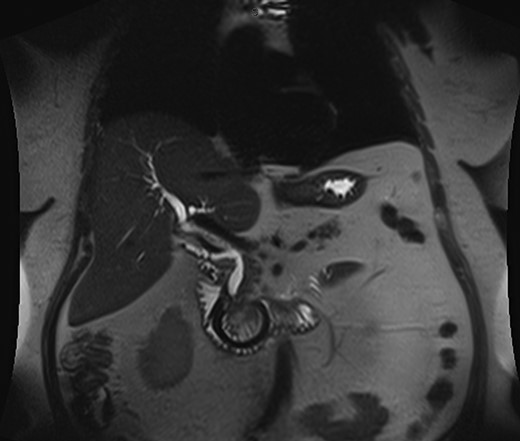

An abdominal ultrasound revealed a dilated common bile duct (CBD) at 10 mm and mild prominence of the left sided intrahepatic duct. The distal CBD was obscured by bowel gas. Patient then proceeded to magnetic resonance cholangiopacreaticogram (Fig. 1), which showed intraluminal migration of the gastric band causing obstruction at the ampulla of Vater.

Magnetic resonance cholangiopacreaticogram (MRCP) preporatively.